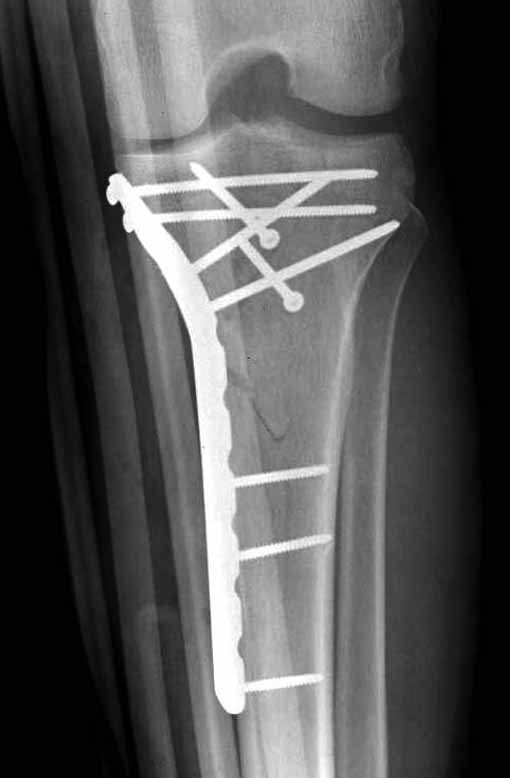

Двухколоннный перелом тибиал плато с вовлечением проксимального диафиза. Внутрисуставной компонент без смещения, и такой перелом можно лечить любым из описанных методов, о которых говорят наши коллеги.

Удобно аппаратом Илизарова или интрамедуллярным гвоздем. Гвозди не так сложно, как пугают, тем более Александр готов помощь с методичкой. Сперва надо установить компрессирующие шурупы на мыщелки. Давно отказались в пользу 3.5-4.0 мм кортикальных вместо толстых спонгиозных, потому что не доказаны преимущества толстых шурупов. Тонкие шурупы в субхондральной зоне смотрятся намного элегантнее, чем толстые 6.5.

Это мероприятие превращает перелом в простой диафизарный, который легко можно фиксировать гвоздем. Шурупы надо установить сзади предполагаемого места введения гвоздя.

Для изолированных переломов медиального тибиал плато, фиксацию можно провести “медиальной пластиной”. Некоторые компании, например Smith & Nephew делают медиальные и медиально-задние пластины, но они мягкие, и легко можно создать нужный контур. Жесткость создается за счет фиксации жесткими пластинами, например экстра артикулярной пластиной для дистального плеча от Synthes. Медиальный доступ тоже не из легких, надо работать между pes and medial gastroc.

Частая ошибка, когда фиксацию двух колонного перелома проводят одиночной пластиной, т.е с одной стороны, и такая фиксация не удерживает, происходит вторичноое смещение. Необходимо нейтрализовать второй пластиной или дополнительным наружным фиксатором.

Если у вас, кроме пластины, нет другого альтернативного варианта, тогда, учитывая мягкотканые проблемы с наружной стороны, я бы рекомендовал операцию делать в два этапа. Преимущества, сперва репозиция и фиксация перелома с медиальной стороны, а затем, после улучшения состояния мягких тканей, зафиксировать с латеральной стороны. Современные пластины имеют латеральный Jig для перкутанных мини доступов.

В приложении этапы фиксации Both Column Fx и пластиной Synthes для плеча при переломе медиального мыщелка.